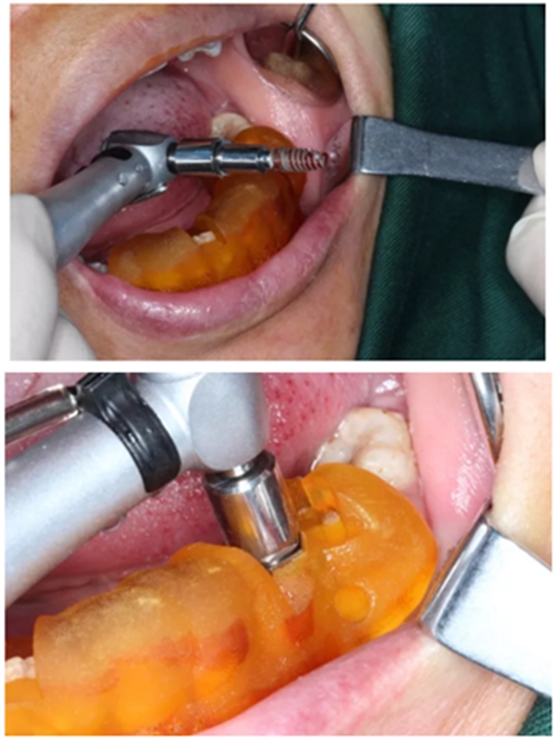

1.碘伏浸泡消毒后的导板在患者口内试戴,就位准确、十分稳固。

2.使用牙龈环切刀施行不翻瓣手术,创伤小,保护患者牙龈软组织形态。

3.根据手术计划书,使用术前所设计好的长度、直径的一系列钻针在导板的引导下进行备孔。

4.在全程导板的引导下,使用全程导板工具盒中的携带器,从导板套环孔处将植体植入,直至携带器的六角、与导板套环的六角严丝合缝(如图,六角对六角),即表示植体就位成功。